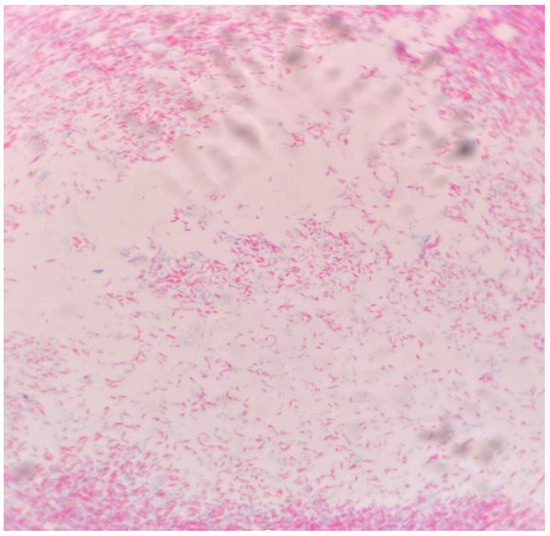

Introduction: Infective endocarditis (IE) is a disease that may frequently lead to significant morbidity and is associated with high mortality rates. Even though IE is classically caused by Gram-positive bacteria, Gram-negative bacteria may seldom ca...